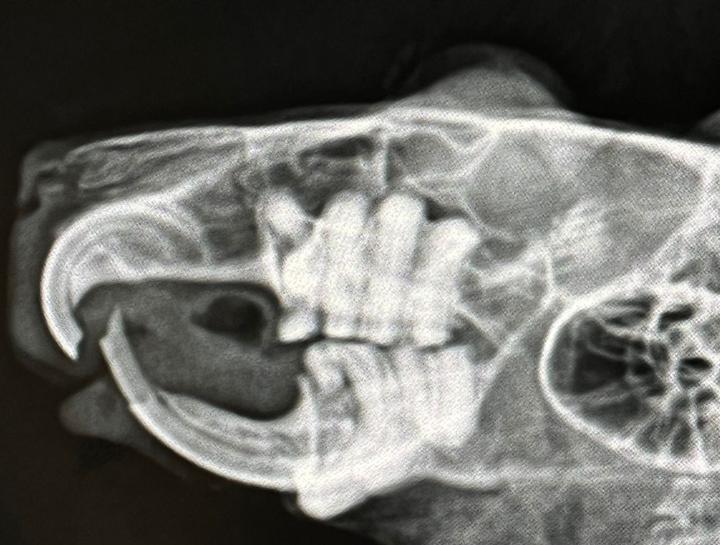

Pet Digital Radiology

Digital x-rays assist in diagnosing illness & injury.